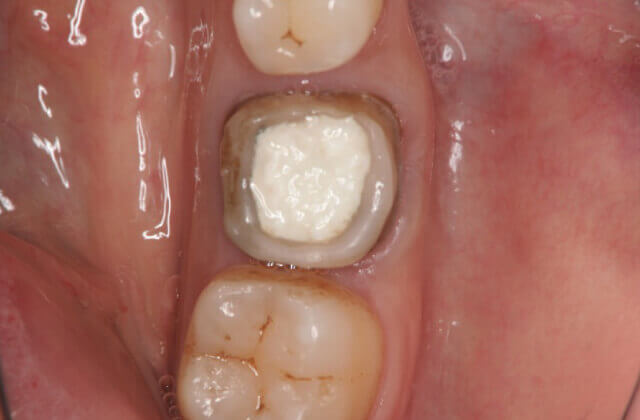

マイクロスコープで歯の内部を確認

(マイクロスコープを使うと歯の中に神経のある管が存在している事が分かります)

マイクロスコープを使用しないで、今までの勘だけに頼った治療を行った場合には、治療後に短期間で再発してしまったり、無症状のまま気がつかずに進行してしまい(抜歯せざるえない状態にまで進行してしまい)インプラントやブリッジ・入れ歯といった治療を受けざる得ないことになりかねません。